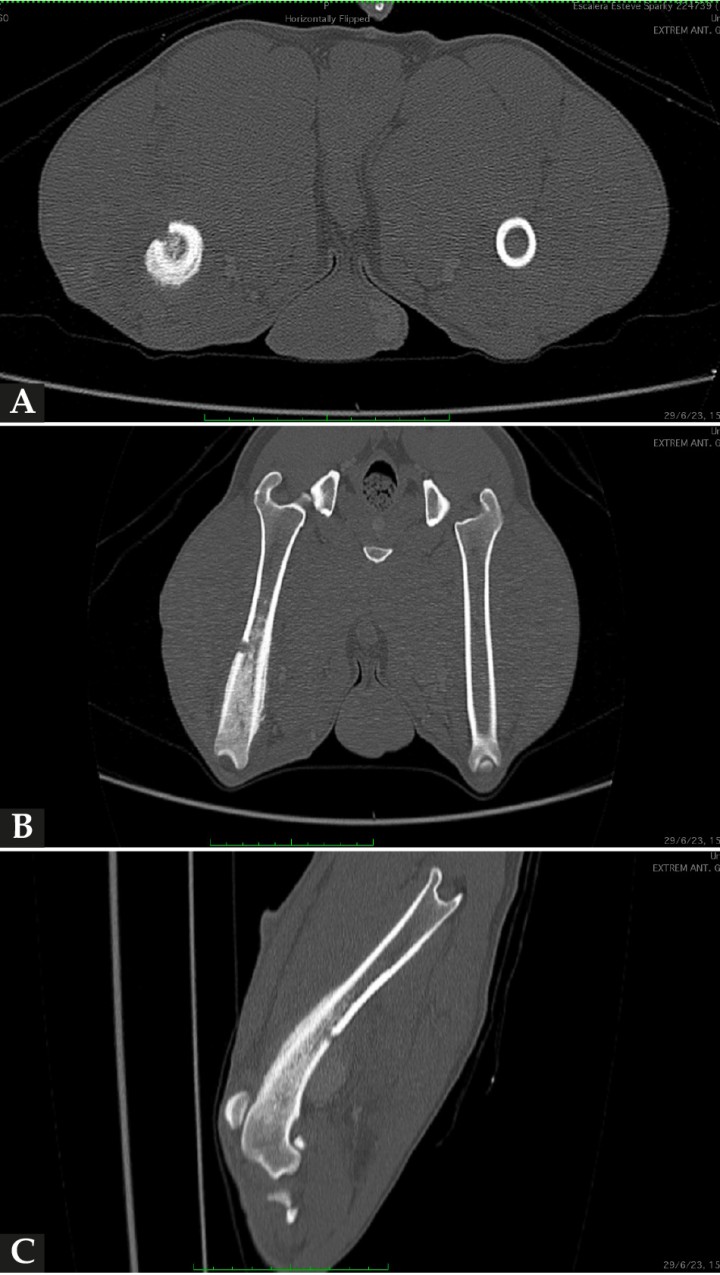

En los tejidos blandos junto al aspecto caudodistal del fémur, se visualizó una estructura redondeada, de 3 cm de diámetro y de atenuación líquido/tejido blando en precontraste, con un realce marcado postcontraste sugestivo de estructura vascular (Figs. 2 y 3). La vena y arteria femoral derecha presentaban apariencia normal hasta el aspecto distal del fémur, donde la vena femoral parecía conectar con la estructura descrita. La arteria femoral quedaba en íntimo contacto con dicha estructura, aunque no parecía estar conectada. Este hallazgo era compatible con una dilatación aneurismática afectando a la vena femoral. Distalmente a esta lesión, la arteria y vena poplíteas se observaban ligeramente más distendidas en comparación al lado contralateral. También había un leve aumento de atenuación de la grasa subcutánea de forma difusa distal a la lesión compatible con edema subcutáneo.

<p>(<strong>A</strong>) Imagen de TC reconstruida en Volumen Rendering (3D), tras administración de contraste (visión caudal). Se observa, caudalmente al aspecto distal de la diáfisis femoral, una estructura redondeada con gran captación de contraste (flechas naranjas) aparentemente conectada con la vena femoral y en íntima relación con la arteria femoral. (<strong>B</strong>) Imagen de TC reconstruida en Volumen Rendering (3D), tras administración de contraste (visión medial oblicua), donde se observa la estructura vascular descrita en (<strong>A</strong>) (flecha naranja).</p>

Figura 3

(A) Imagen de TC reconstruida en Volumen Rendering (3D), tras administración de contraste (visión caudal). Se observa, caudalmente al aspecto distal de la diáfisis femoral, una estructura redondeada con gran captación de contraste (flechas naranjas) aparentemente conectada con la vena femoral y en íntima relación con la arteria femoral. (B) Imagen de TC reconstruida en Volumen Rendering (3D), tras administración de contraste (visión medial oblicua), donde se observa la estructura vascular descrita en (A) (flecha naranja).